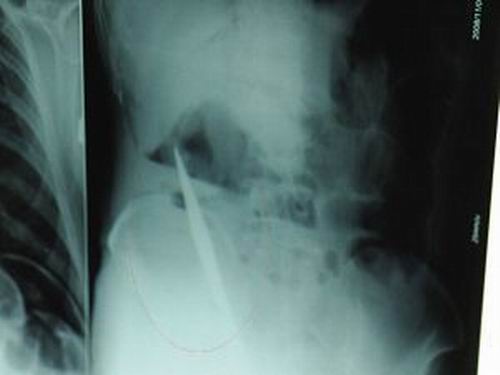

X光片上,尖刀清晰可見。

從男子體內(nèi)取出的尖刀足足有19厘米長(zhǎng)。

江蘇銅山一58歲男子因服毒被送到醫(yī)院搶救,可醫(yī)生采取搶救措施后卻發(fā)現(xiàn)效果不佳。后來經(jīng)細(xì)致檢查,醫(yī)生有了個(gè)驚人的發(fā)現(xiàn),該男子的體內(nèi)竟然有一把尖刀,醫(yī)生通過手術(shù)將位于其腹部右側(cè)橫結(jié)腸下緣的尖刀取了出來。這把尖刀足足有19厘米長(zhǎng)!據(jù)醫(yī)生推測(cè),這把刀應(yīng)該是從肛門推進(jìn)體內(nèi)的,不知男子為何想以如此殘酷的方式結(jié)束自己生命。由于搶救及時(shí),該男子已暫時(shí)脫離危險(xiǎn)。

昨天(11月6日)上午,記者在徐州礦務(wù)集團(tuán)總醫(yī)院重癥監(jiān)護(hù)室見到了這名男子,目前他雖然已經(jīng)恢復(fù)了意識(shí),但還不能開口說話,需要呼吸機(jī)輔助呼吸。據(jù)醫(yī)生介紹,4日中午12時(shí)左右,這名男子因服毒輕生被緊急送到醫(yī)院進(jìn)行搶救,之前,這名男子已經(jīng)在當(dāng)?shù)剜l(xiāng)鎮(zhèn)醫(yī)院進(jìn)行了近20小時(shí)的治療,但效果不佳。“病人被轉(zhuǎn)院到礦總院時(shí)已神志不清,血壓極低,處于休克狀態(tài)。”救護(hù)人員給男子洗胃、初步處理以后,發(fā)現(xiàn)男子呼吸急促,于是趕緊給他拍片檢查。結(jié)果讓所有的醫(yī)生大吃一驚,竟有一把尖狀異物橫在該男子腹腔內(nèi)!當(dāng)天下午5時(shí)30分,輕生男子被推上了手術(shù)臺(tái)。經(jīng)過40多分鐘的手術(shù),該男子腹腔被打開,手術(shù)醫(yī)生發(fā)現(xiàn),男子體內(nèi)的金屬狀異物竟然是一把長(zhǎng)19厘米的尖刀!

醫(yī)生告訴記者,手術(shù)后,醫(yī)生在病人身上并未發(fā)現(xiàn)刀痕,最后,經(jīng)過檢查發(fā)現(xiàn),在該男子直腸處找到穿孔。醫(yī)生從醫(yī)學(xué)角度分析后認(rèn)為,這把尖刀應(yīng)該是從肛門插入直腸的。